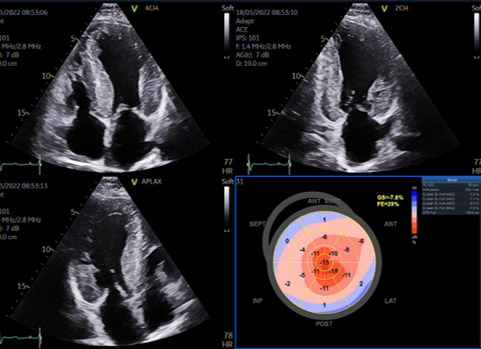

En échocardiographie, une augmentation d’épaisseur septale dès 12 mm doit alerter et faire pratiquer une étude Doppler tissulaire à l’anneau mitral et un strain global longitudinal avec recherche d’un aspect en cocarde (Figure 1) avec déformations à l’apex beaucoup moins pathologiques que les déformations à la base aux segments moyens.

Figure 1 : Amylose TTR héréditaire . 64 ans

Cet aspect est fréquent, évocateur mais pas pathognomonique du diagnostic ; de plus, si la coupe apicale est de mauvaise qualité, si le ventricule gauche est tronqué, il y aura un aspect en cocarde, mais uniquement parce que l’apex n’est pas dans l’image ! La rigueur des acquisitions des coupes apicales en échocardiographie transthoracique est donc fondamentale.